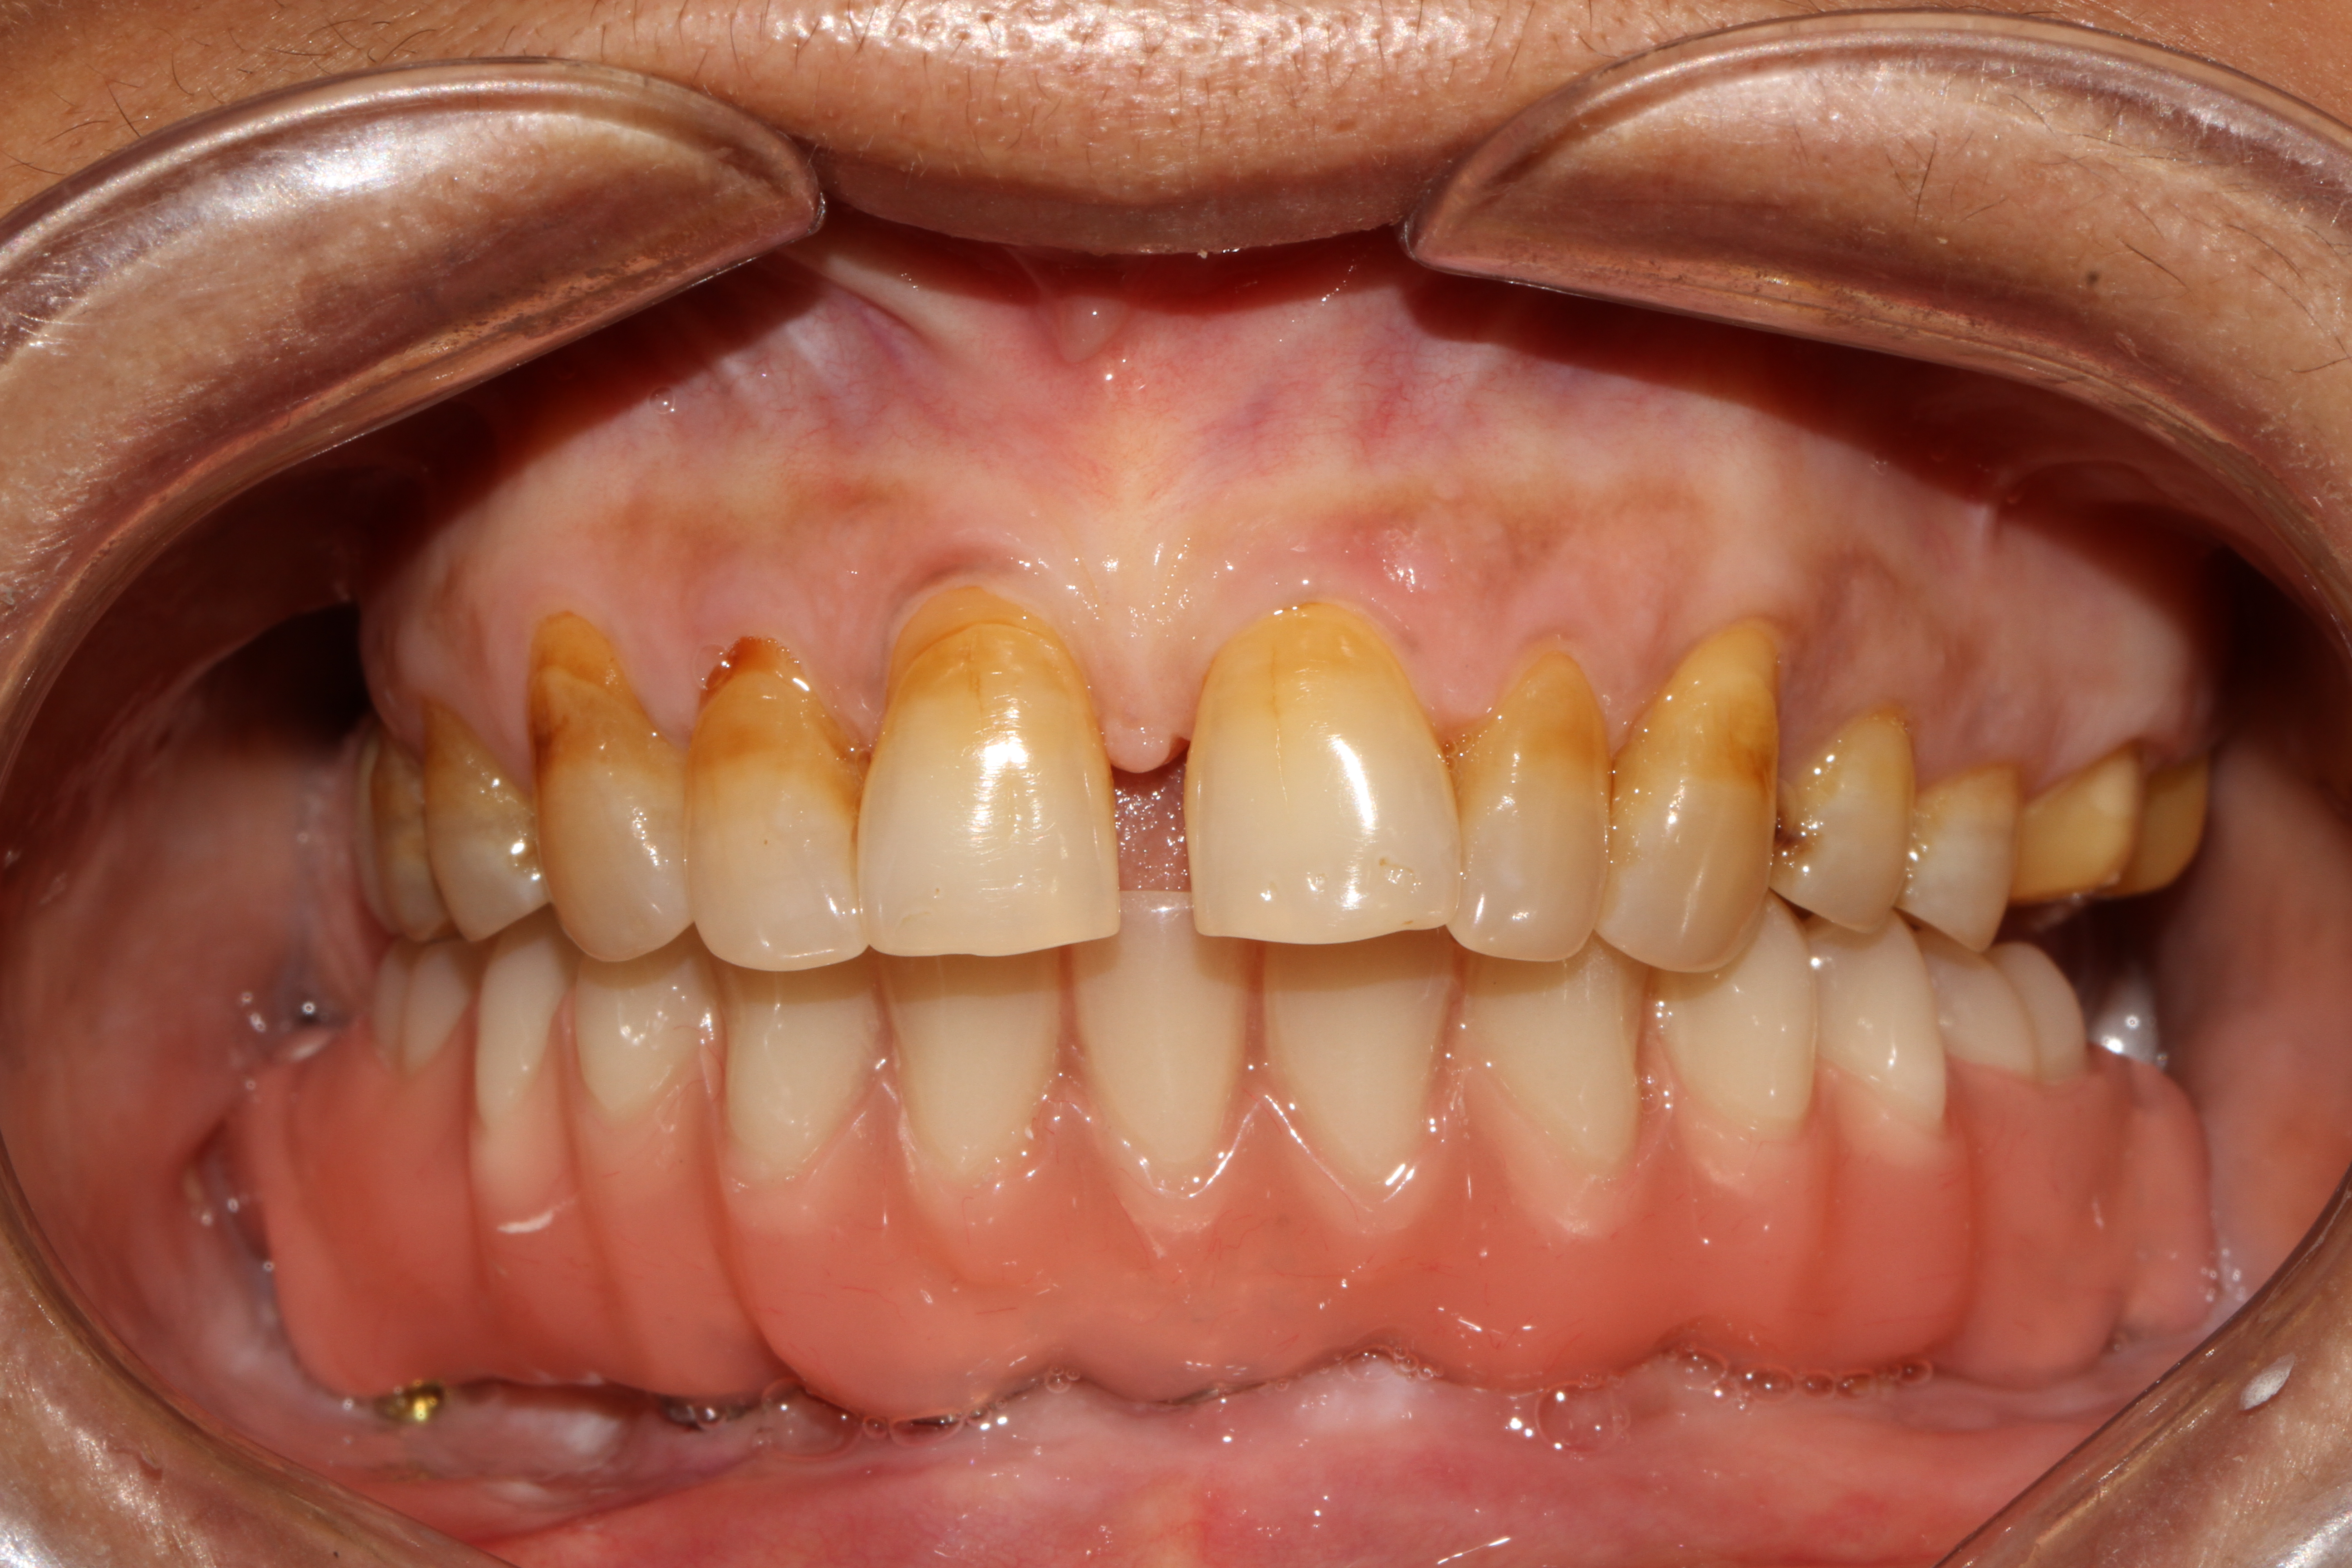

When it comes to replacing the entire arch of a lower jaw with 14 teeth, options like replacement with a zirconia crown, which is free of metal or porcelain fused to metal (ceramic) crown can be used. These crowns are fabricated in our hi-tech lab in 3 days which is fixed with the new generation of immediate loadable single piece implant. At Jani's Implant Cantre and Smile Studio, basal implants with a combination of crestal implants are used. Using this art of implant placement all 14 teeth which include the second molars are replaced. The introduction of second molars by this step will help the patient chew in a more efficient way similar to that of natural teeth. depending upon the patient's medical status, oral health and the quality of the bone, 6-8 implants are placed on which 14 teeth (full arch) is fixed. This is a full mouth immediate loadable implant therapy for the lower jaw. This is done in the form of permanent teeth in 3 days protocol where no bone augmentation and bone grafting is needed.